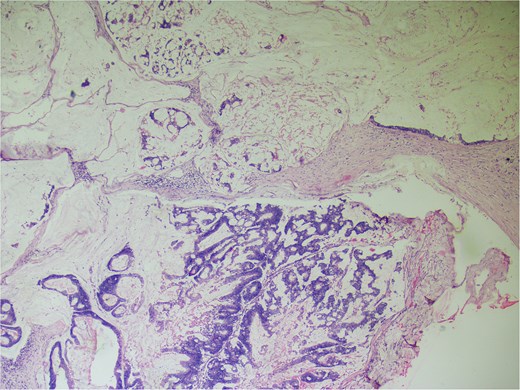

On gross examination, growth seen involving ileocecal junction extending upto caecum measuring 6.5 × 6.0 × 4.3 cm. Cut section showed solid creams white firm to friable areas with mucoid consistency at places. A nodular growth is identified in the attached mesentery measuring 3.5 × 2 × 2 cm. On cut section solid white areas are seen along with focal area showing mucoid consistency. The histopathological report concluded mucinous adenocarcinoma of caecum, pT3N1MX, with evidence of lymphovascular invasion. The tumor invaded through the muscular propria layer (Figs 4 and 5). Additionally, acute appendicitis was found.

Hemotoxylin and eosin ×100: Section shows atypical cells floating in lates of extra cellular mucin.

Hematoxylin and eosin ×40: Section shows lymph node effacement of by pool of mucin and few atypical cells and the periphery show compressed lymphoid tissue.